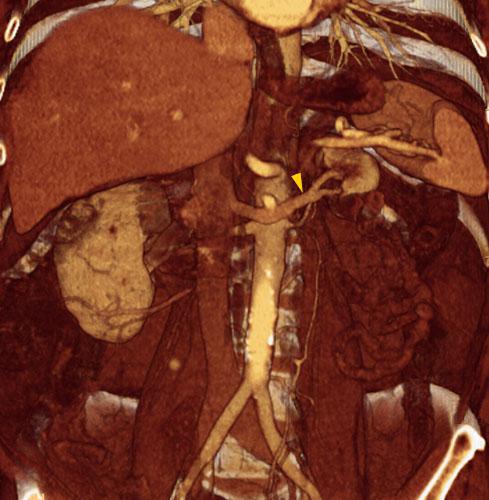

Hipoplasia renal 2